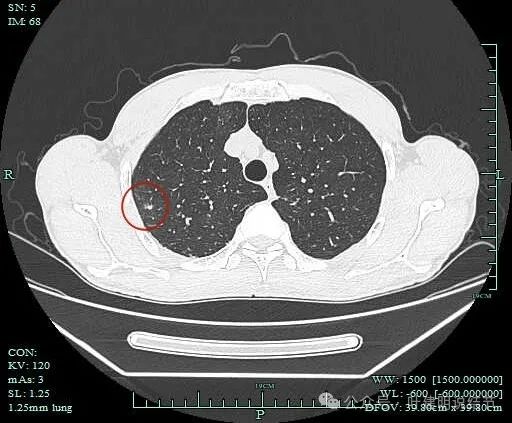

病灶2:

病灶出现,密度杂乱。

有磨玻璃成分,且轮廓清,磨玻璃边缘有细毛刺征,实性成分的边缘毛糙不平,形态不规则。

灶内有僵硬支气管走行,边上少许磨玻璃成分,病灶有一定收缩力。

灶内支气管穿行且显得僵硬。

胸膜牵拉,灶内支气管通气征并显僵硬,部分边缘有毛刺征。

有血管进入并异常增粗;病灶有分叶征,有毛刺征,也有胸膜牵拉征。

病灶有细毛刺征,感觉有收缩力。

实性成分为主,边上少许磨玻璃成分。

叶间胸膜牵拉。

这个病灶是非常典型的恶性的,总体上基本上是实性成分,但边上仍有少许磨玻璃,而磨玻璃成分有分叶与细毛刺,病灶内部有支气管通气征,且支气管显僵硬,又有异常增粗的血管进入。再加上胸膜牵拉、叶间裂牵拉,整体轮廓较清,周围肺野清爽,没有卫星灶。所以基本上就是浸润性癌了的。